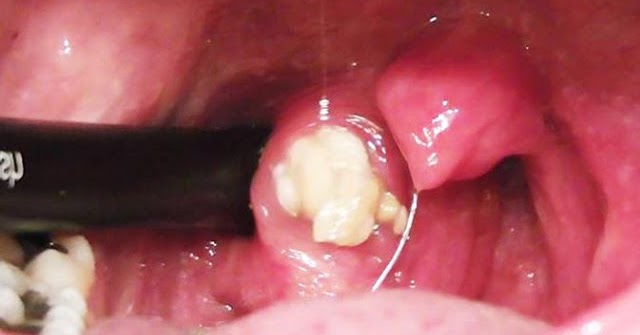

Arti mimpi melihat batu yaitu: Anda akan ketemu dengan seseorang yang mempunyai sifat pelupa, keras kepala bodoh, pemalas, dan sangat merugikan Anda dalam pekerjaan. Sebagaimana hal nya sifat-sifat dari batu. Arti Mimpi Melempar atau Dilempar Batu Melempar Batu Ke Laut Arti Mimpi Menarik Rambut Di Mulut. Mimpi ini mengatakan kamu akan mengalami masalah yang terjadi pada kesehatan. yakni panas dalam atau pernafasan, penyakit kuning, dan sariawan. 4. Arti Mimpi Mengeluarkan Batu. Mimpi mengeluarkan batu dari mulut yakni kamu mempunyai nasib penuh kesialan dan buruk.